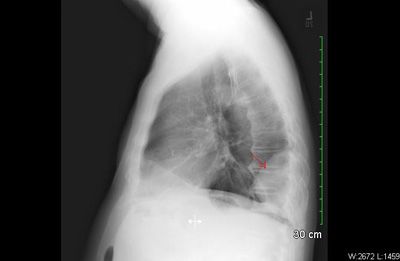

A 76-year-old man presented with left-sided chest pain after a fall. Chest films showed non-displaced fractures of the 7th and 8th ribs with a small effusion and a right postero-basal rounded opacity. A CT scan showed the 8th rib fracture and a prominent pleural-based soft tissue mass in the right lower lobe. Video-assisted thoracoscopic surgical technique was used to resect the mass. The histopathology showed a 9-cm solitary fibrous tumor (SFT) of the pleura, with negative margins.